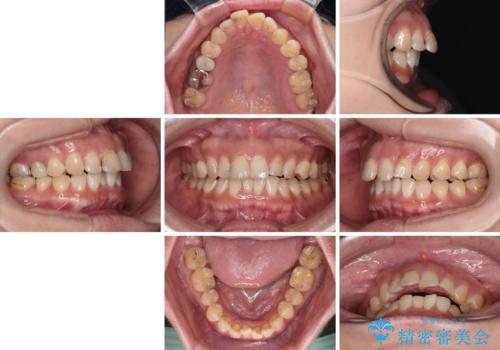

- 飛び出た上の前歯を気にして来院された患者様です。

奥歯の咬み合わせは、上顎歯列が理想的な一よりも数mm前方にある状態でした。

なるべく早めに治療を終えたいとのことで、補助装置を用いて上顎臼歯を後方に移動させ、同時にワイヤー装置にて整えることとしました。